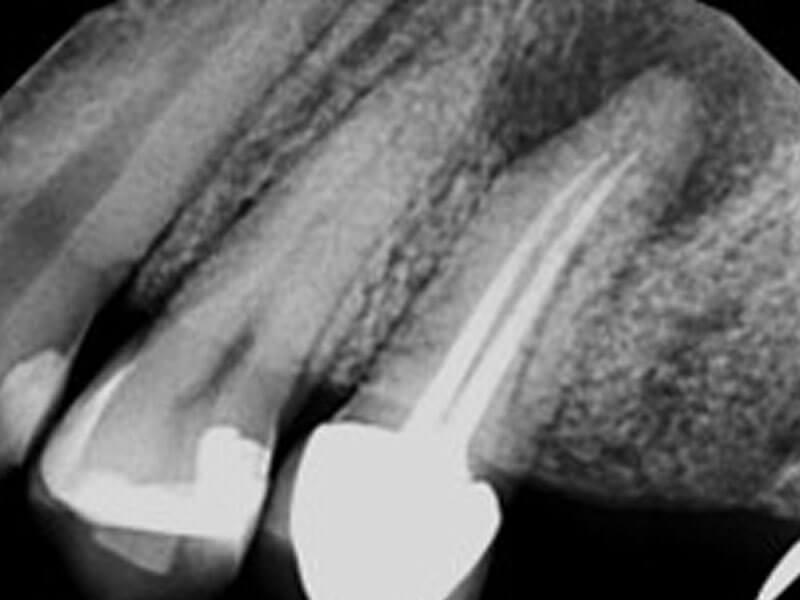

Patient was referred for apical surgery after previous endodontic treatment was unsuccessful. After retreatment with the GentleWave® Procedure with ProControl™, adjusting NaOCl to 5%, the patient's symptoms completely resolved within 48 hours.